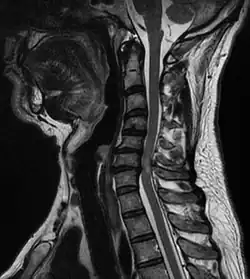

Eine zervikale Myelopathie ist eine Schädigung des Rückenmarks der Halswirbelsäule, des Cervikalmarks.

In der Halswirbelsäule liegen die Verhältnisse anders: Bandscheibenschäden oder andere, raumfordernde Prozesse können, wenn sie sich an einer ungünstigen Stelle ereignen, zu einer Schädigung des Rückenmarkes führen. Wenn der Bandscheibenvorfall nicht genau in der Mitte auf das Rückenmark drückt, kommt es meistens zu einer „Halbseitensymptomatik“. Missempfindungen in einer Körperhälfte, Reflexdifferenzen, auch Störungen der Bewegungskoordination können die Folge sein. Oft wird ein „Stromgefühl“ angegeben, das bei manchen Stellungen der Halswirbelsäule wie ein Blitz durch eine Körperhälfte zuckt. Je nachdem, wie groß der Vorfall ist, kann es auch zu einer, mehr oder weniger kompletten, „hohen Querschnittssymptomatik“ kommen, neben der Funktion der Arme und Beine sind dann auch die Atemmuskulatur oder die Kontrolle von Blase und Enddarm betroffen.